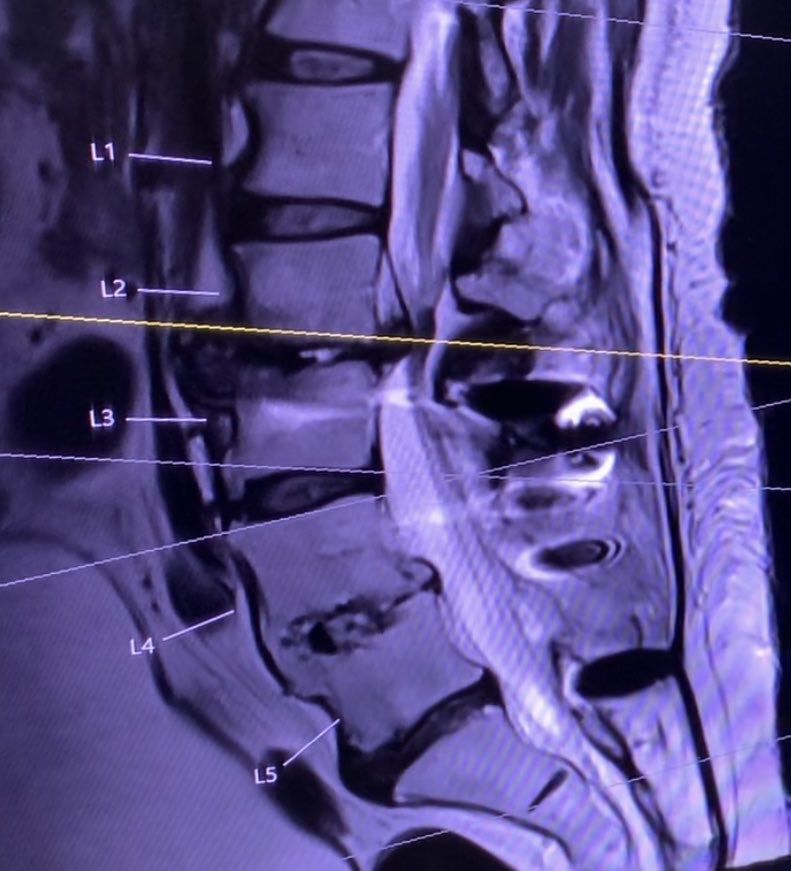

Given her severe positive SVA surgical plan was a L5/S1 ALIF, L2-4 OLIF, and posterior L2-Pelvis instrumented fusion. The olif was challenging given the grade 3 spondy but an expandable trial helped with the reduction. @CNS_Update @spinesection